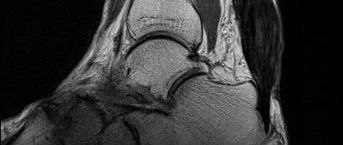

女性,双侧跟腱进行性增粗,活动略受限,请诊断!